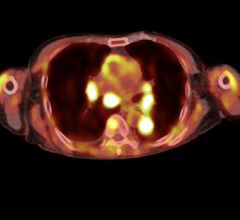

MVision, from Siemens Medical Solutions, is a volumetric in-line target imaging solution and the natural next step in Image Guided Radiation Therapy (IGRT). Designed to work with Siemens' linear accelerators, the system is the first commercial implementation of cone-beam technology utilizing a standard radiotherapy treatment beam. MVision makes it possible for the megavoltage (MV) source used for treatment to also create a 3-D image of the patient, enabling clinicians to "see inside" the patient at the most appropriate moment.

MVision fully integrates and automates all processes, including acquisition, reconstruction, registration, assessment, patient positioning and clinical review. With a few steps, therapists can calculate 3-D offsets, send them to the treatment couch to compensate for daily variations and safely deliver therapy.